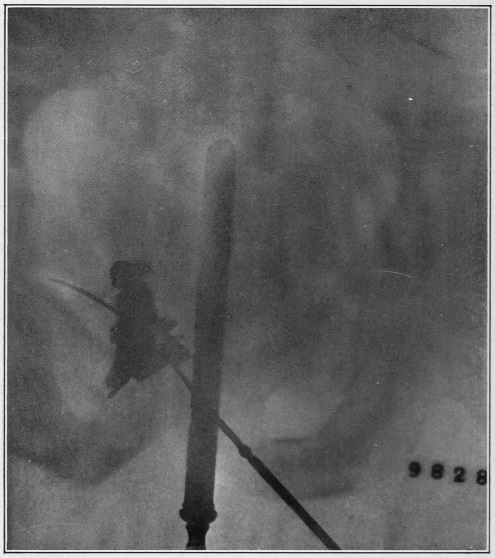

Nine Radiograph Illustrations Showing Mucus Channels and Cavities200

Fig. 4.

1, The dotted lines indicate the normal direction of the anus and rectum; 2, 4, the cavities or pouch formed by dilatation or ballooning from the storage of impacted feces; 3, a probe bent at right angles, and introduced through a speculum, to ascertain the depth of the pouch, which is frequently found to be two and a half inches.